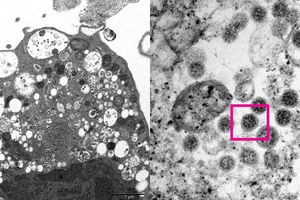

Ngày 8/12, các nhà khoa học tại trường Đại học Hong Kong đã công bố hình ảnh đầu tiên về biến thể Omicron dưới kính hiển vi điện tử.Theo đài Sputnik (Nga), các chuyên gia y tế, bao gồm nhà nghiên cứu bệnh lý học và nhà virus học, đã chụp lại hình ảnh hiển vi điện tử của tế bào thận khỉ (Vero E6) sau khi con vật này nhiễm biến thể Omicron. Mới đây, họ đã đã công bố hình ảnh của biến thể này ở độ phóng đại thấp và cao.

Các nhà nghiên cứu giải thích ở độ phóng đại thấp, hình ảnh cho thấy các tế bào bị tổn thương với các nang sưng tấy chứa các hạt virus nhỏ màu đen. Trong khi ở độ phóng đại cao, hình ảnh cho thấy tập hợp các hạt virus tròn có gai trên bề mặt.Theo báo cáo, các nhà nghiên cứu từ Khoa Vi sinh vật học tại Đại học Hong Kong đã tìm cách phân lập Omicron từ các mẫu bệnh phẩm lâm sàng, điều này sẽ cho phép giới khoa học phát triển và sản xuất vaccine chống lại biến chủng mới.